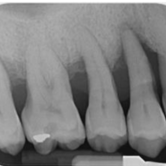

Reabsorción Externa

La reabsorción externa es la pérdida de tejido dental desde el exterior del diente hacia adentro, a menudo como resultado de un trauma o infección.

Los pacientes pueden no tener síntomas hasta que el diente se afloje.

El tratamiento incluye la eliminación de la causa y, a veces, un tratamiento de conducto. En casos severos, puede ser necesario extraer el diente.